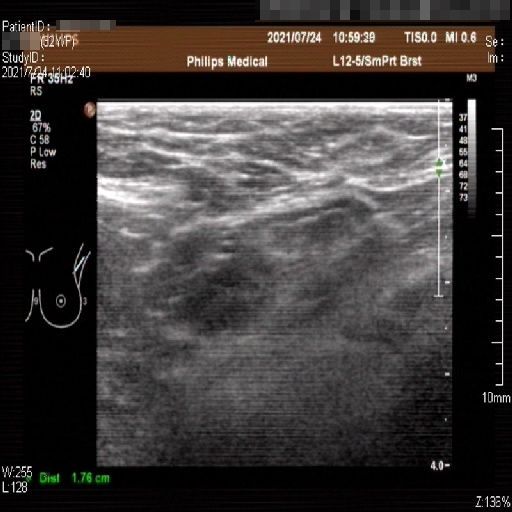

Images with certain annotations are considered noisy images in the context of the noise removal task, and corresponding images without these annotations are considered clean. Some typical images with various annotation are provided in Fig. 1.

The radial line annotation is pairs of connected cross markers. They are usually placed at the edge of the lesion area, with its placement determined by the size of the lesion. One to three pairs of cross markers may be present in an image, corresponding to the three axes of 3D space, but typically there are only two pairs.

Refer to caption

Figure 1: Images with various annotations. (a) body marker annotation, (b) radical line annotation, (c) vascular flow annotation.